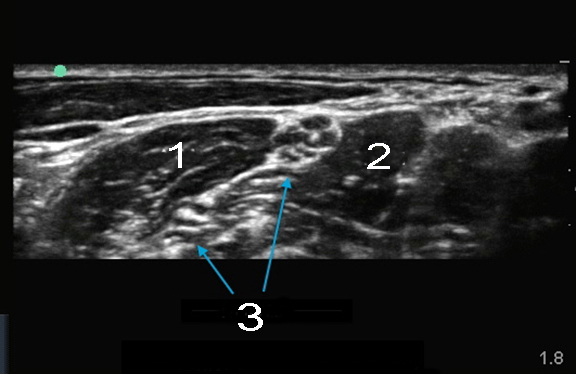

EDGE: Interskalenär 2

Nerven